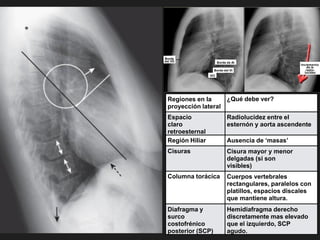

Regiones en la

proyección lateral

¿Qué debe ver?

Espacio

claro

retroesternal

Radiolucidez entre el

esternón y aorta ascendente

Región Hiliar Ausencia de ‘masas’

Cisuras Cisura mayor y menor

delgadas (si son

visibles)

Columna torácica Cuerpos vertebrales

rectangulares, paralelos con

platillos, espacios discales

que mantiene altura.

Diafragma y

surco

costofrénico

posterior (SCP)

Hemidiafragma derecho

discretamente mas elevado

que el izquierdo, SCP

agudo.